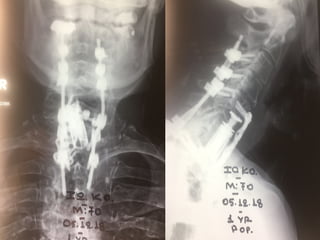

Late post traumatic Lumbar instability and Kyphosis

Pre operative plan

Intraoperative correction and stabilization

Post operative x-rays

Lumbar – Sacral – Iliac

stabilization

Pre - operative

Post operative